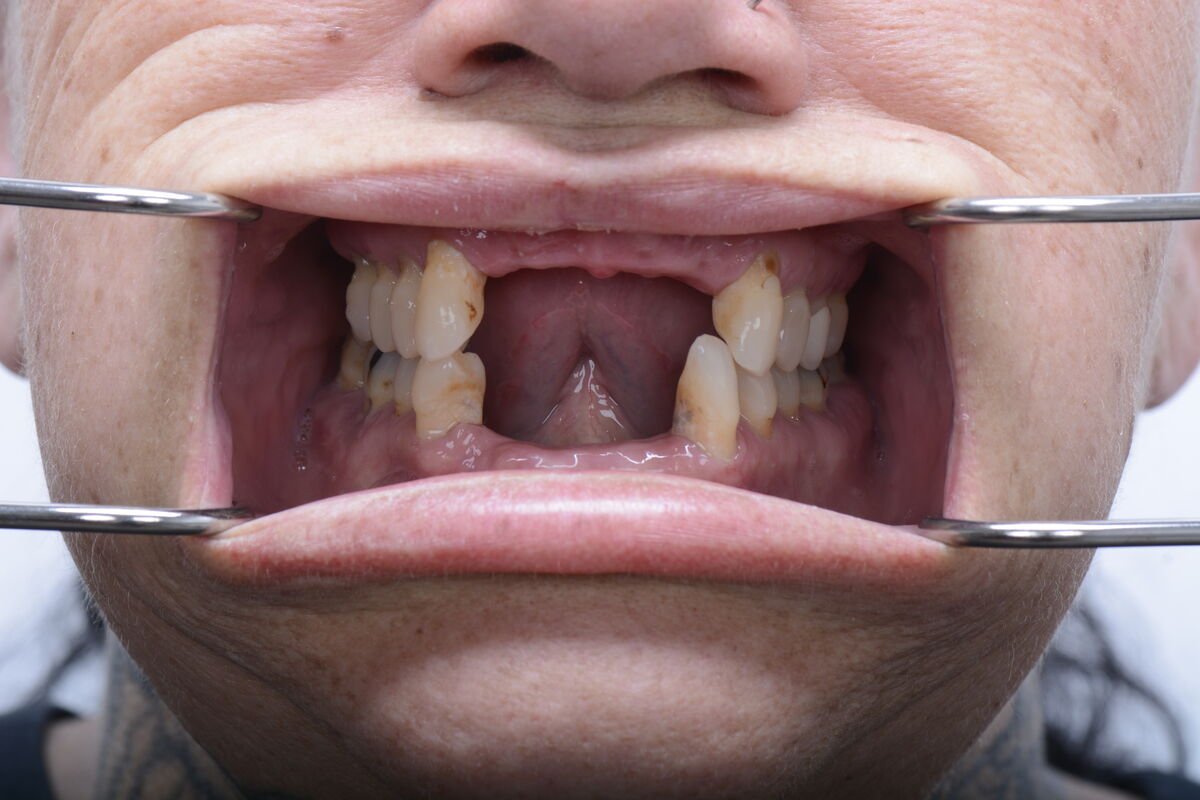

Real Smile Transformations

See the life-changing results from real patients who chose Fusion Dental Implants.